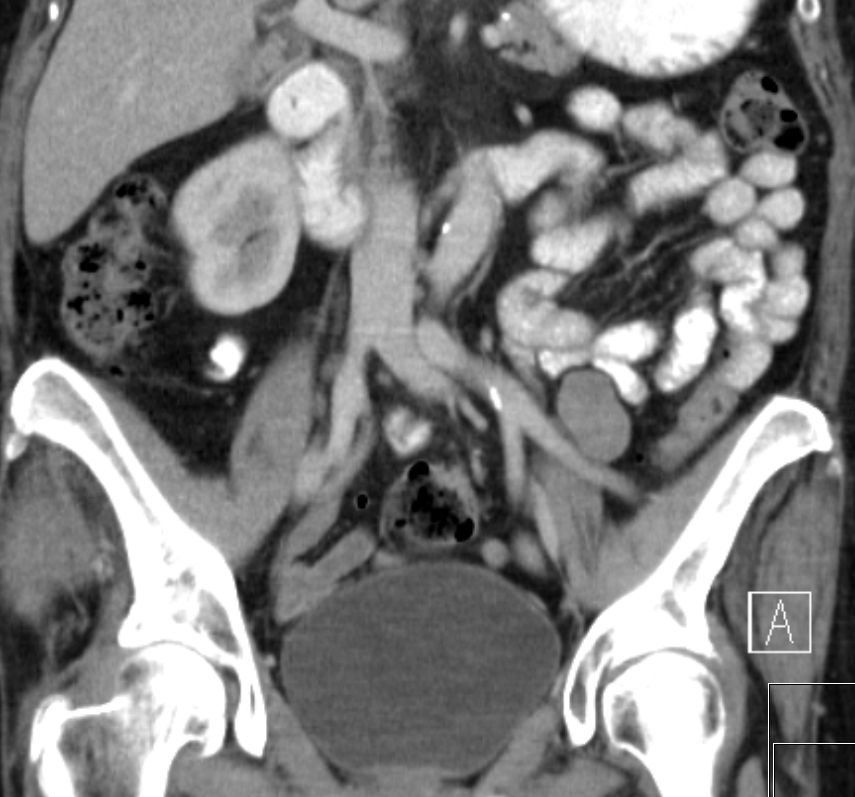

| Metastasierung | vergrößerten Lymphknoten lateral der A. iliaca externa links